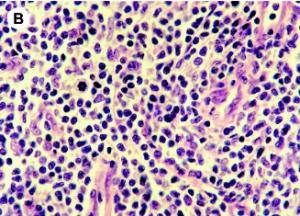

Les infections bactériennes sont d'ailleurs plus fréquentes chez les patients atteints de lymphome cutané dont la peau est plus fragile. Ces infections se multiplient avec le développement de la maladie. Le lymphome cutané à cellules T ou « T cutané » est caractérisée par une prolifération de cellules T malignes dans un environnement inflammatoire chronique. Avec la progression de la maladie, bactéries colonisent la barrière cutanée et la moitié des patients décède de l'infection plutôt qu'en raison de la malignité. Des données cliniques ont déjà montré le rôle direct des bactéries dans la progression de ce cancer. Cette étude décrypte les voies moléculaires de ce rôle bactérien.

In vitro, l'équipe montre à partir de prélèvements de tissus de peau affectée de patients atteints, et d'isolats bactériens qu'une toxine de Staphylococcus aureus (staphylococcal enterotoxin-A /SEA) stimule l'expression de 2 protéines, STAT3 et IL-17, dans les cellules T malignes ce qui favorise l'activation d'une voie oncogénique établie bien documentée dans le développement du cancer (carcinogenèse). En bref, via ses toxines, la bactérie « profite » aux cellules cancéreuses et favorise leur croissance. Dans le lymphome cutané, des cellules immunitaires spécifiques, les lymphocytes T CD4+ se transforment en cellules cancéreuses. L'étude montre que les toxines des bactéries permettent aux cellules cancéreuses d'envoyer des signaux qui perturbent le mécanisme de défense immunitaire, qui normalement devrait lutter contre les cellules cancéreuses. Les bactéries pourraient donc contribuer à rendre le lymphome de la peau soudainement plus agressif chez certains patients.